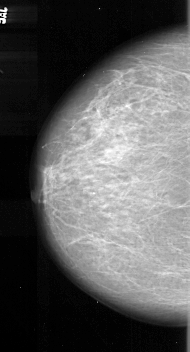

A_1081_1.RIGHT_MLO

RIGHT_MLO LINES 5881 PIXELS_PER_LINE 3286 BITS_PER_PIXEL 16 RESOLUTION 42 OVERLAY